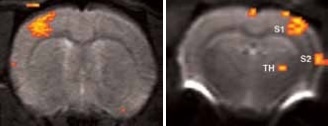

Matrices up to 256 x 256 were obtained with a four-element array coil, resulting in 75 x 75 x 1000 μm3 resolution. The activation becomes more resolved at this high resolution and allows the detection of sub-structures and shape in thalamus areas S1 and S2, as shown in Figure 3.

High resolution BOLD activation at 11.7 Tesla using the four-element array coil with a resolution of 75 x 75 x 1000 μm3 for detection of (left) sub-structures within S1, and activation within other regions along the neuronal pathway: S2 and thalamus

Figure 3. High resolution BOLD activation at 11.7 Tesla using the four-element array coil with a resolution of 75 x 75 x 1000 μm3 for detection of (left) sub-structures within S1, and activation within other regions along the neuronal pathway: S2 and thalamus. Image Credit: Bruker BioSpin Group

When the forepaw is electrically stimulated, the thalamus, and primary (S1) and secondary (S2) somatosensory corte are activated. To achieve this, electrical pulses (1–2 mA of 0.3 ms duration, at 6 or 3 Hz) are applied for 15 seconds after a resting period of 45 seconds, repeated 5 times. It takes 5 minutes and 45 seconds for the resultant total scan.